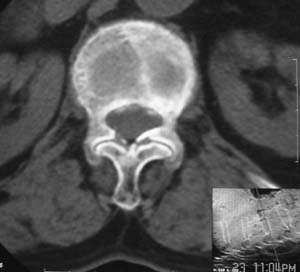

患者,女,72岁,胸背部疼痛3月余,无明显外伤史。曾应用局部封闭、非甾体类止痛药治疗效果不明显,近来疼痛缓解频感背困,平卧缓解,近日行ct检查发现胸12椎体病变,烦请同道发表意见,诊断什么?有何治疗经验!谢谢!!!

标绘图示:第十二胸椎级第一腰椎椎体楔形改变。ct扫描示:第十二胸椎椎体骨质结构紊乱,并可见一囊状低密度影,边缘可见硬化,椎体皮质完整。

考虑:第十二胸椎陈旧性骨折、许莫氏结节。